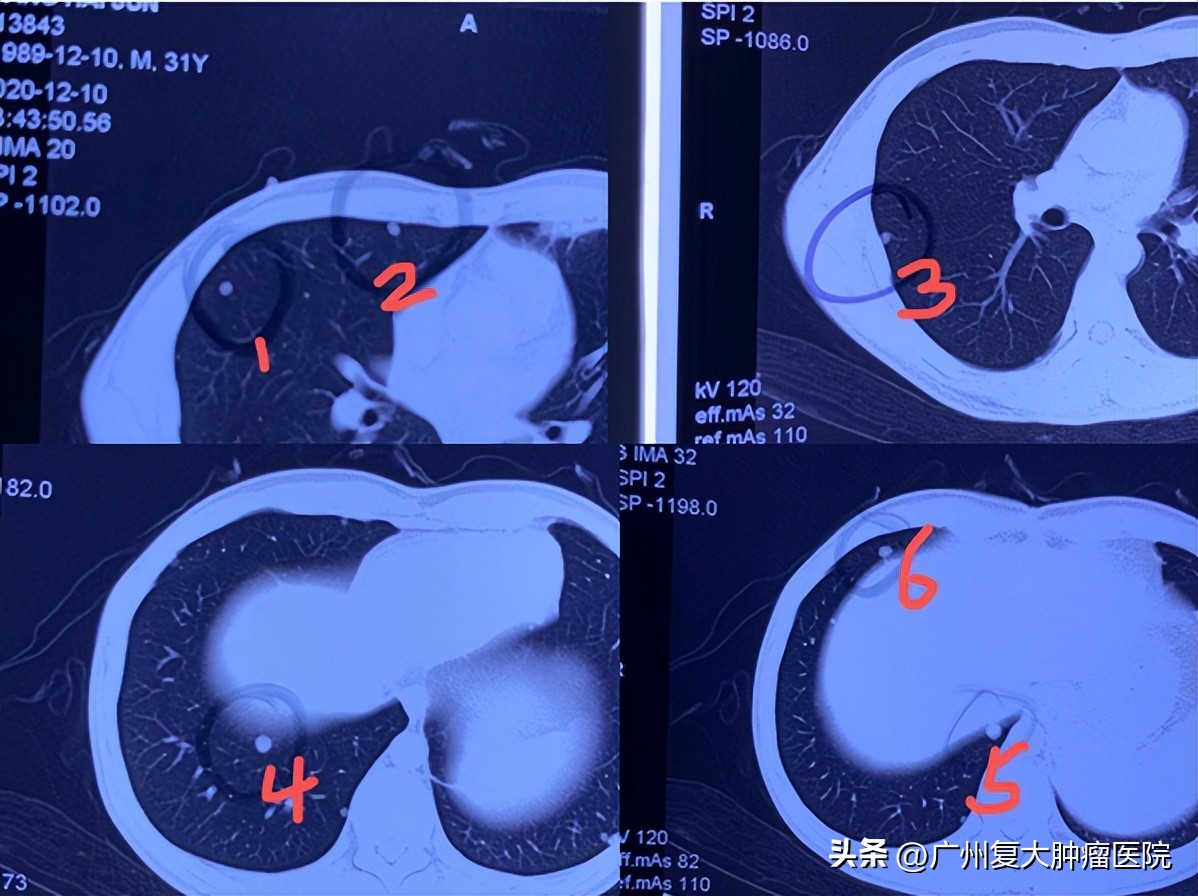

这是一位患有肝癌的患者,经过手术切除以后,在后续的观察期间,发现了肺部的转移。吃过靶向药后,肺部的情况控制得还可以。但是问题在于,肺部现在有六个肺结节没有消失。这六个肺结节持续存在,也没有缩小。这六个病灶明显不适合手术了。患者经过咨询,来到广州复大肿瘤医院,找到了牛立志院长团队,寻求更有效的治疗。

但是,对于这位患者,分两次做消融,一来会增加患者的费用,二来也会耽误很多时间,让患者受到两次创伤。这位患者比较年轻,而且肺功能比较好,牛立志院长“艺高人胆大”,一次性为患者冷冻消融掉了六个结节。一次消融后,六个肺结节全部灰飞烟灭,避免了患者的二次伤害。